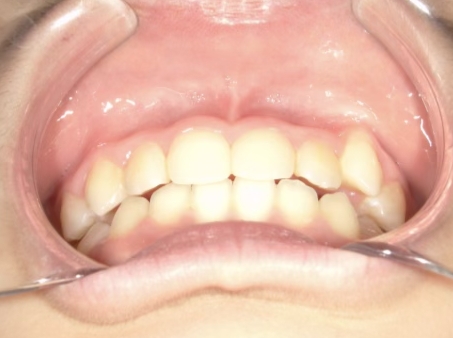

治療前① 小1:6y8m 初診

| カウンセリング・診断結果 | 前歯の生え変わり時期に来院されました。(写真①) 乳歯列期に受け口の既往があり切端咬合になりそうなため、受け口に対する矯正治療の考え方と対処法、当院のコンセプトを説明したところ治療を希望されたので診断を行いました。 診断の結果、上顎骨に対し下顎骨が長く、骨格的な構造も下顎突出型反対咬合(下顎骨が適切な位置よりも前に出ているタイプの受け口)と分かりました。 顔立ちは、中顔面が引っ込んだように見えるコンケーブに移行中です。 機能的な問題として低位舌があるため受け口の悪化が考えられることも説明し、以下の治療を提案しました。 |